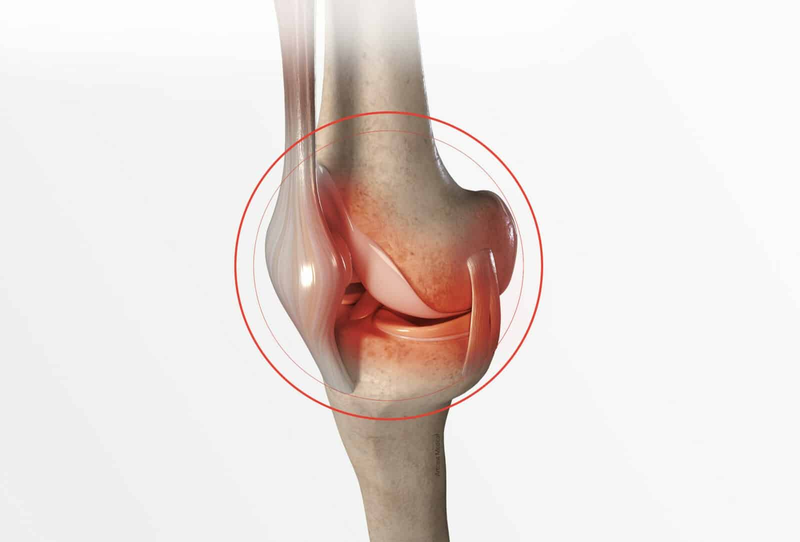

• Viêm khớp: Viêm khớp gối và viêm khớp hông do thoái hóa hoặc viêm nhiễm.

• Chấn thương dây chằng: Rách dây chằng gối và dây chằng chéo trước do xoay hoặc kéo căng mạnh.

• Trật khớp gối: Xảy ra khi xương bị lệch khỏi vị trí ban đầu, gây đau và sưng.

• Bệnh lý xương bánh chè: Viêm xương bánh chè do chấn thương hoặc căng thẳng kéo dài.